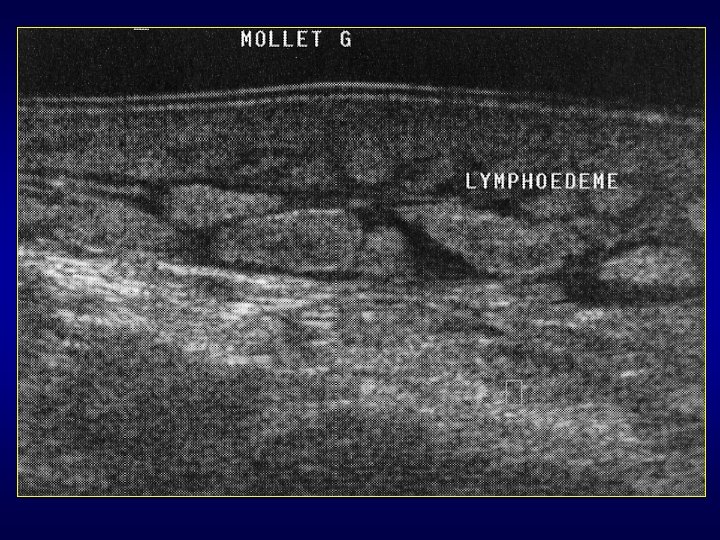

Est-ce vraiment un processus expansif? • Pièges : muscle accessoire, hernie musculaire, lésion musculaire traumatique, ténosynovite, moignon d’une rupture ligamentaire, hernie digestive, bursite, corps étranger en particulier plantaire, abcès (ddf avec tumeur nécrosée difficile +++), hématome (parfois ddf difficile avec T peu vascularisée), récidive post-op ou lymphoedème?

Malformations veineuses • • = malformation vasculaire la + fqte Cuisse et mollet +++ Masse musculaire sensible à palpation Pas de pulsatilité ni de thrill Rx: phlébolithes Echo: masse serpigineuse hypoéchogène IRM: lobules HT 2, calcifications, graisse Souvent multifocale: musculaire et souscutanée